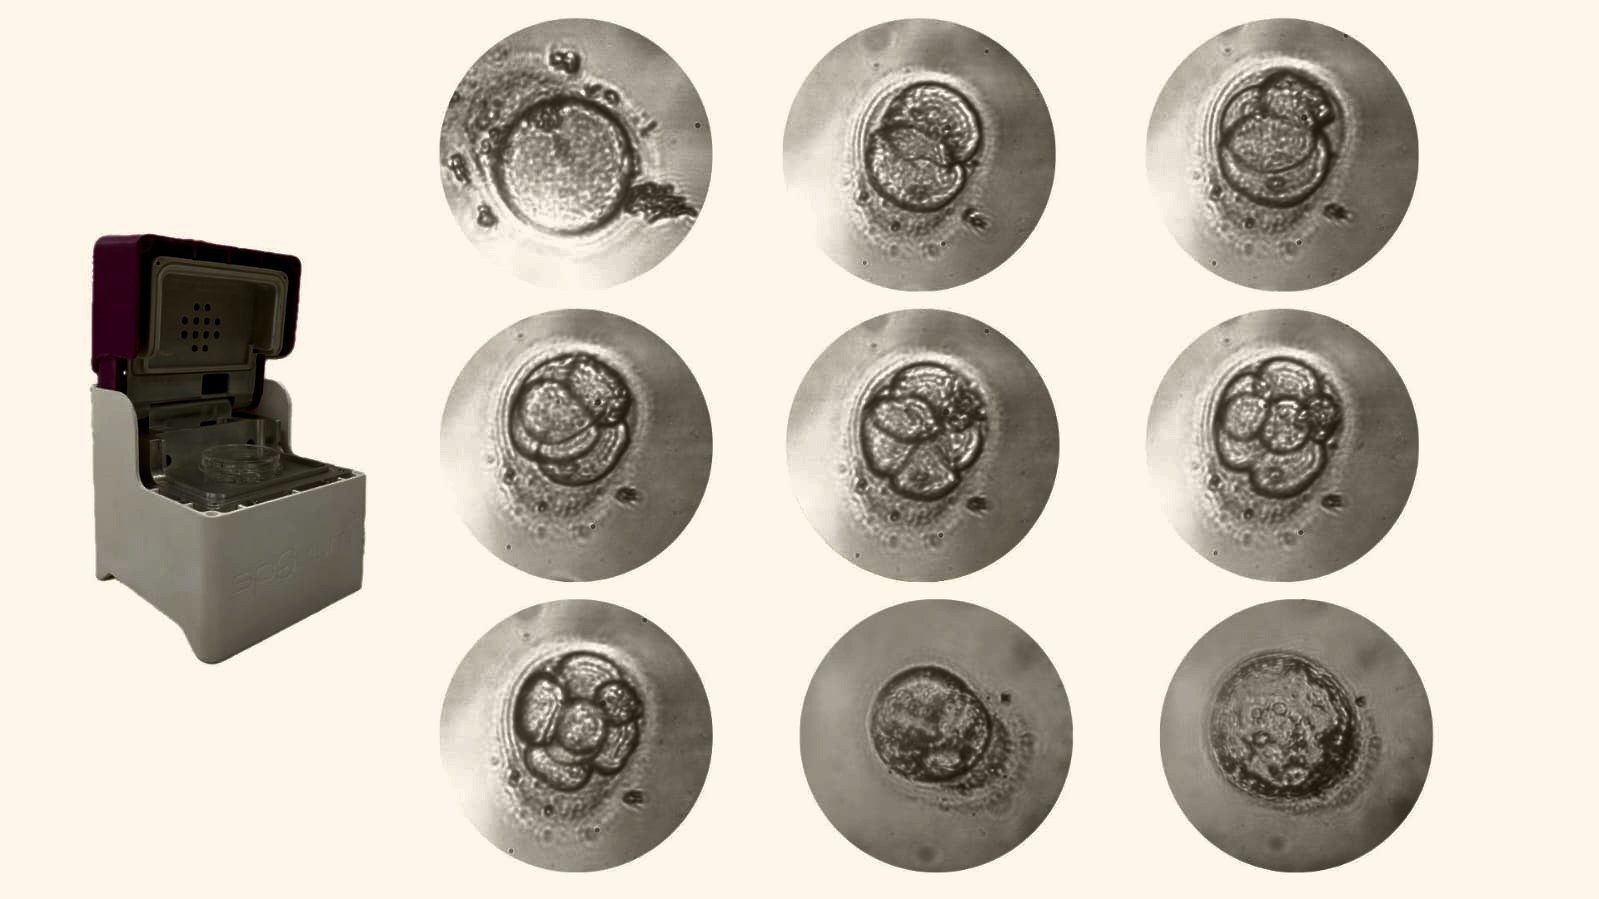

Section 3 Image

Time Lapse Monitoring

Continuous Embryo Monitoring,High resolution Imaging ,AI-powered Analysis, Cloud-based storage and Enhanced quality control